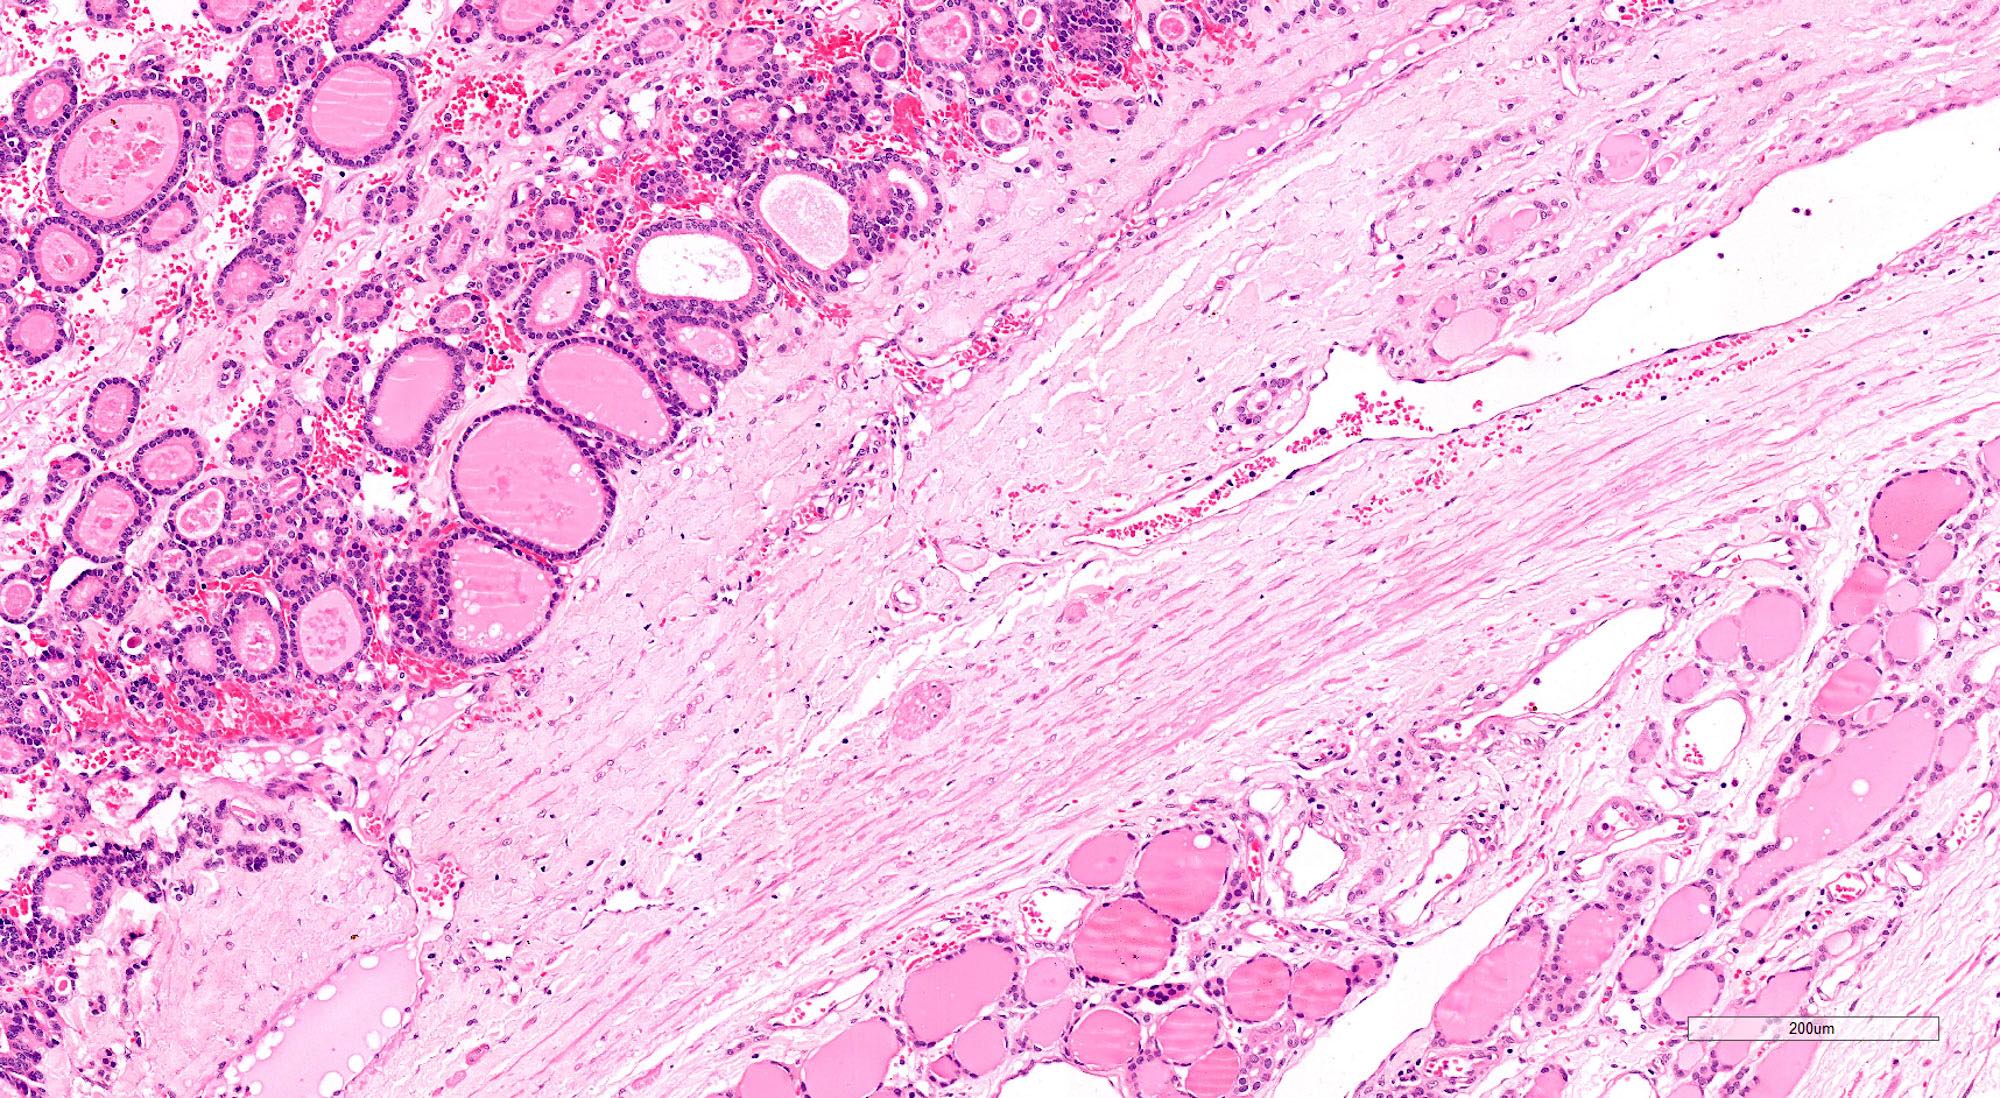

Microscopic (histologic) description

- Architecturally and cytologically different from surrounding gland

- Compression signs in surrounding thyroid tissue

- Encapsulated; thin or moderately thick capsule

- Architectural patterns (can be seen in any combination)

- Normofollicular (simple): size similar to normal thyroid follicles

- Microfollicular (fetal): smaller follicles, small amount of intraluminal colloid

- Macrofollicular (colloid): large follicles, flattened epithelium, abundant colloid

- Solid / trabecular (embryonal): minimal or no colloid

- Focal papillary pattern, occasionally; especially in hyperfunctioning adenoma and follicular adenoma with papillary hyperplasia

- Cuboidal to low columnar cells

- Small round nuclei, smooth nuclear boundary, uniformly hyperchromatic or euchromatic, dense chromatin, absent nuclear features of papillary thyroid carcinoma, nuclear score 0 or 1 (JAMA Oncol 2016;2:1023)

- Inconspicuous nucleoli

- Rarely, lipid filled vacuoles in cytoplasm

- Mitoses are uncommon

- Scant stroma

- Secondary changes: fibrosis, hyalinization, hemorrhage, hemosiderin deposition, edema, cystic degeneration, calcification, osseous or cartilaginous metaplasia

Microscopic (histologic) images

Contributed by Shipra Agarwal, M.D., Andrey Bychkov, M.D., Ph.D., Mark R. Wick, M.D., Asmaa Gaber Abdou, M.D. and AFIP

Patterns: